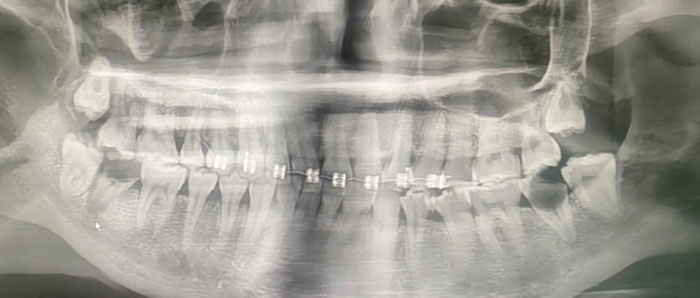

โพสต์ดังกล่าว ระบุว่า Line เด้งจาก Somporn Keawnim หัวหน้าตึกหอผู้ป่วยวิกฤตหัวใจ เคสจริงที่หมอเจอ… น้องอายุเพียง 20 ปี เริ่มจากจัดฟันแฟชั่นในกรุงเทพฯ ฟันผุ มีหนอง เชื้อเข้ากระแสเลือด ตรวจพบเชื้อ Streptococcus gordonii กลายเป็นเยื่อบุหัวใจติดเชื้อ (Infective Endocarditis) สุดท้ายลิ้นหัวใจรั่ว ต้องผ่าตัดเปลี่ยนลิ้นหัวใจ ทั้งที่ยังอายุน้อยมาก

จัดฟันแฟชั่นทำมาจาก กทม. เมื่อประมาณ 6 เดือนที่แล้ว เริ่มมีอาการไอ หายใจไม่ค่อยสะดวก จึงโทร. หาแม่ แม่เลยพามารักษาที่น่าน น้องอายุเพียง 20 ปี แม่ให้ลาออกจากงานเพื่อมารักษาตัวให้หายก่อน